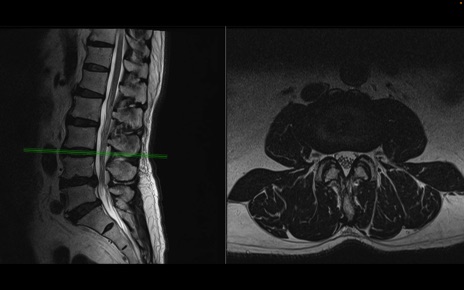

【整形】TIPS症例2 腰椎MRI 横断像と矢状断像

【症例】70歳代男性

【主訴】左下肢痛

【現病歴】2週間前くらいから腰痛、左下肢痛あり。左臀部から大腿、下腿外側のしびれが常時ある。歩行とともに同部位の痛みあり。

【身体所見】Lasegue70-/60+、Bragard-/±、PTR ±/±、ATR -/-、IP 5/5、TA 5/4、TS 5/5、EHL 右第1足趾なし/3、FHL 5/5、hypersthesia(-)、足背動脈触知良好

異常所見と診断は?